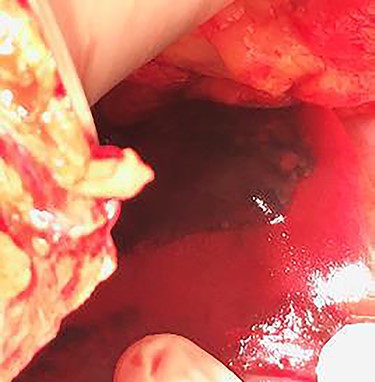

Thirty-one-year-old pregnant woman, primigravida, with history of obesity, admitted at 35 weeks of gestation due to pain in the right abdomen with 2 weeks of evolution. On admission: hemodynamically stable with tenderness on the right quadrants of the abdomen. The initial blood work only revealed thrombocytopenia (120 × 103/μl) and impaired hepatic function (AST 65 U/L, ALT 88 U/L). The patient was kept on observation, with aggravation of symptoms. Blood work showed anemia (6.9 g/dl), thrombocytopenia (113 × 103/μl) and impaired hepatic function (AST 363 U/L, ALT 399 U/L, LDH 505 U/L). The patient underwent an emergency c-section, during which an extensive hemoperitoneum was observed. It was then converted to median laparotomy in which was observed hepatic rupture of segments V, VI and VII; packing was performed and the abdomen closed. A second-look laparotomy was performed 48 hours later. Two new subcapsular hematomas were found in the left lobe, but without active hemorrhage, which led to the removal of the packing (Figs 3–5).